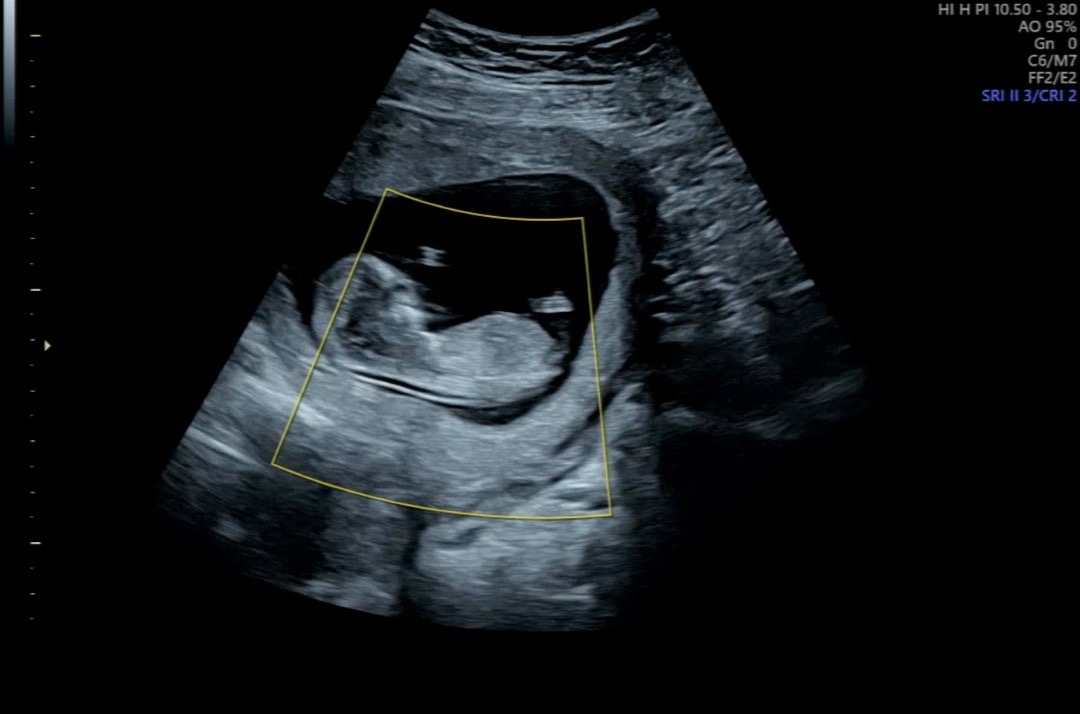

12주 각도법

의사쌤이 다리사이에 아직 아무것도 안보이는데 안만들어진거라 성별을 알수 없다고 하셨어요~ 혹시나 하고 각도법 아시는분 있으신지 올려봅니당